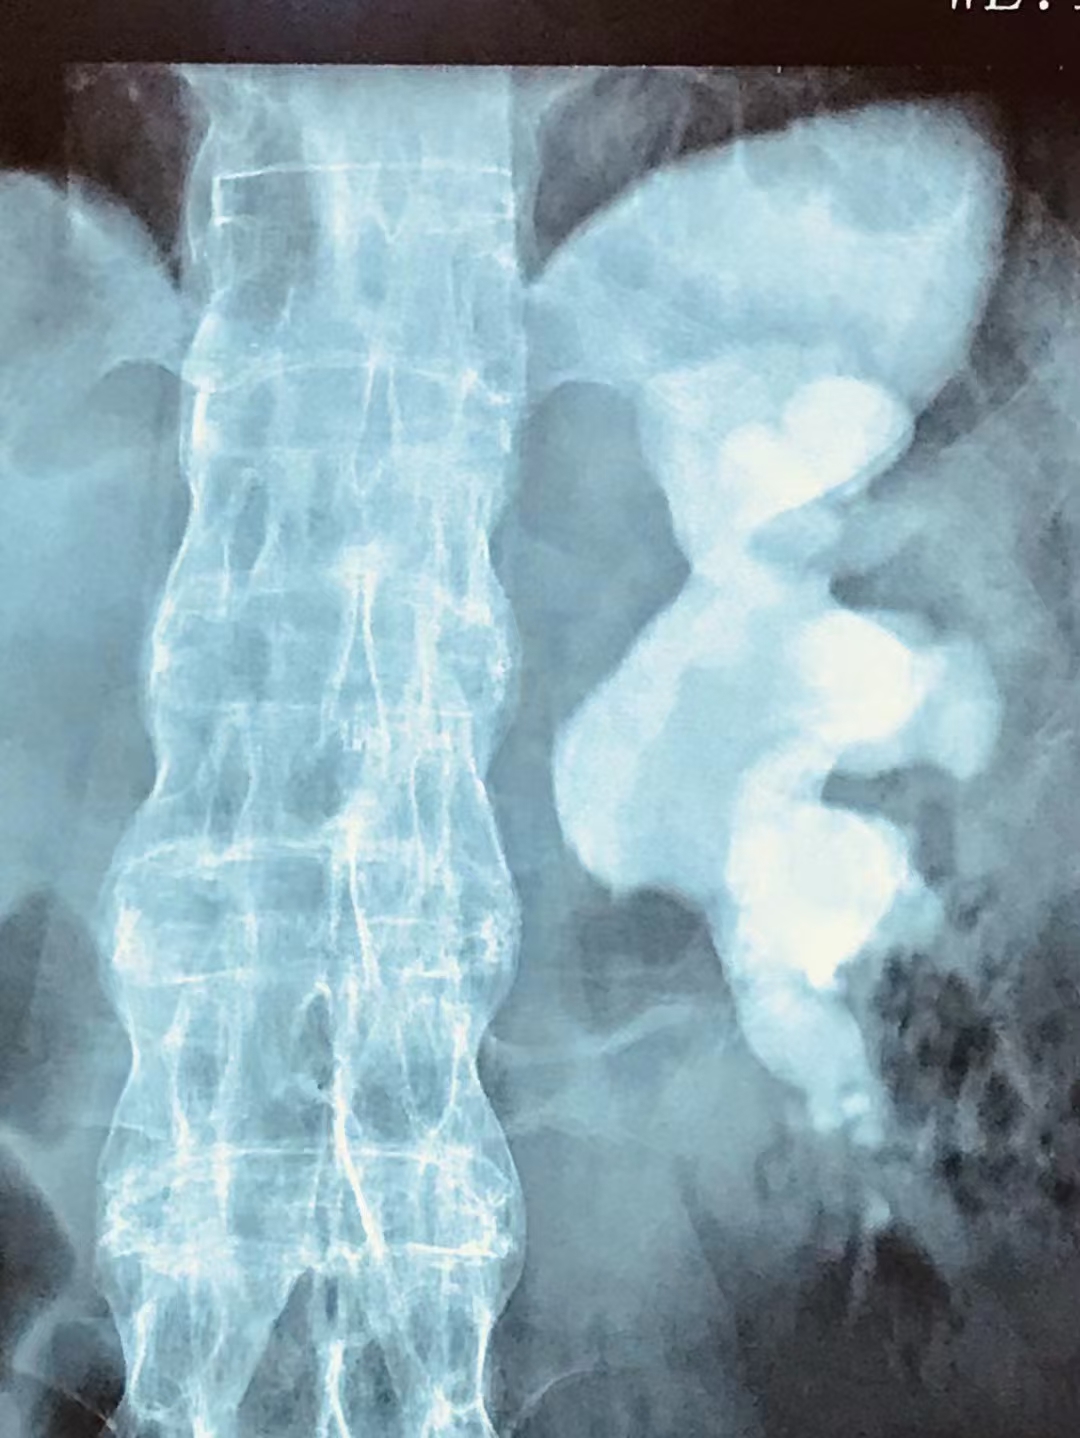

48岁的张师傅是一名司机,一次意外就医,拍片结果却让他傻了眼——他不仅患有肾结石,而且结石还把他的整个肾脏都撑满了。结石都这么大了,可张师傅平时竟没有不舒服的情况,这到底是怎么回事?

一般体积较大的结石,如像张师傅这样的铸型结石,结石与肾内结构相吻合,所以不易移动,如果未引起肾盏肾盂的梗阻或感染,则可能长期存在没有任何症状。

结石如果长期放任不管,它会在体内不断增大,最终填满整个肾脏,形成铸型结石。这类结石如不及时处理,结石不断增大挤压肾脏实质,可导致肾实质变薄、萎缩,甚至肾功能完全丧失。

▲铸型结石

像张师傅这种结石体积、个头比较大的铸型结石,具有分布繁琐、复发率高、手术难度高且取石困难等特点,可能需要多次手术才能处理干净,住院周期也更长。